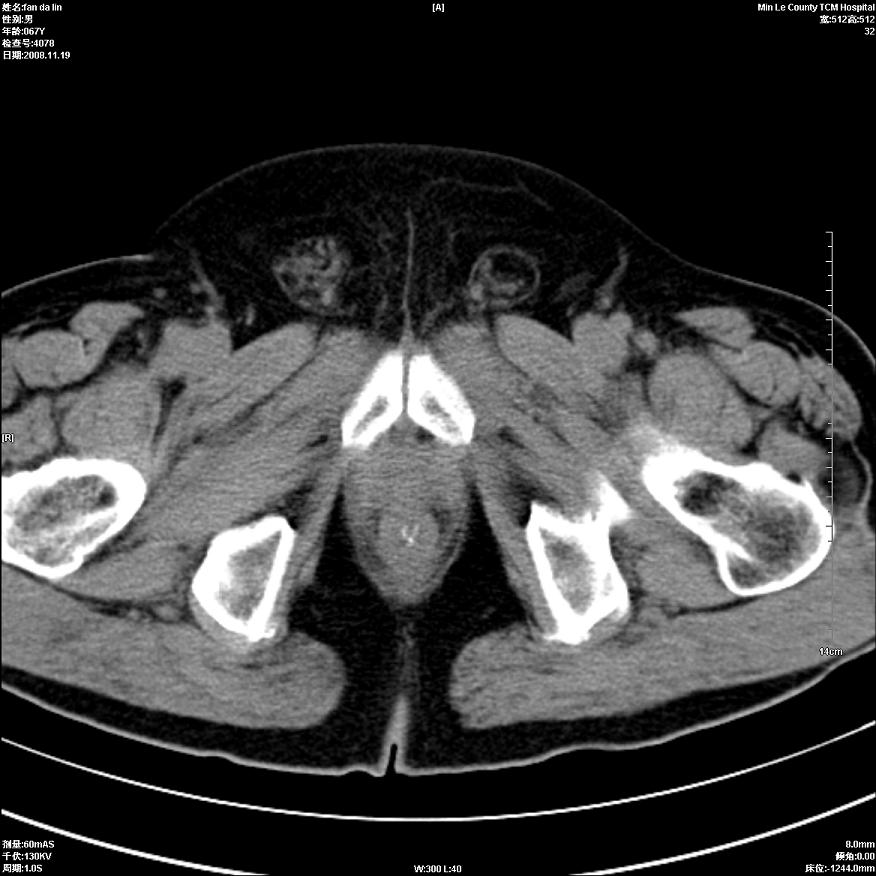

标题: CT16698:M67Y,看看直肠下端是不是病变 [打印本页]

标题: CT16698:M67Y,看看直肠下端是不是病变

粘膜皱壁,不除外内痔

直肠及乙状结肠管壁均增厚,考虑炎症.

直乙交界处肠壁不规则增厚,还是做个肠镜吧

只是肠壁局限性增厚,但难说明问题。